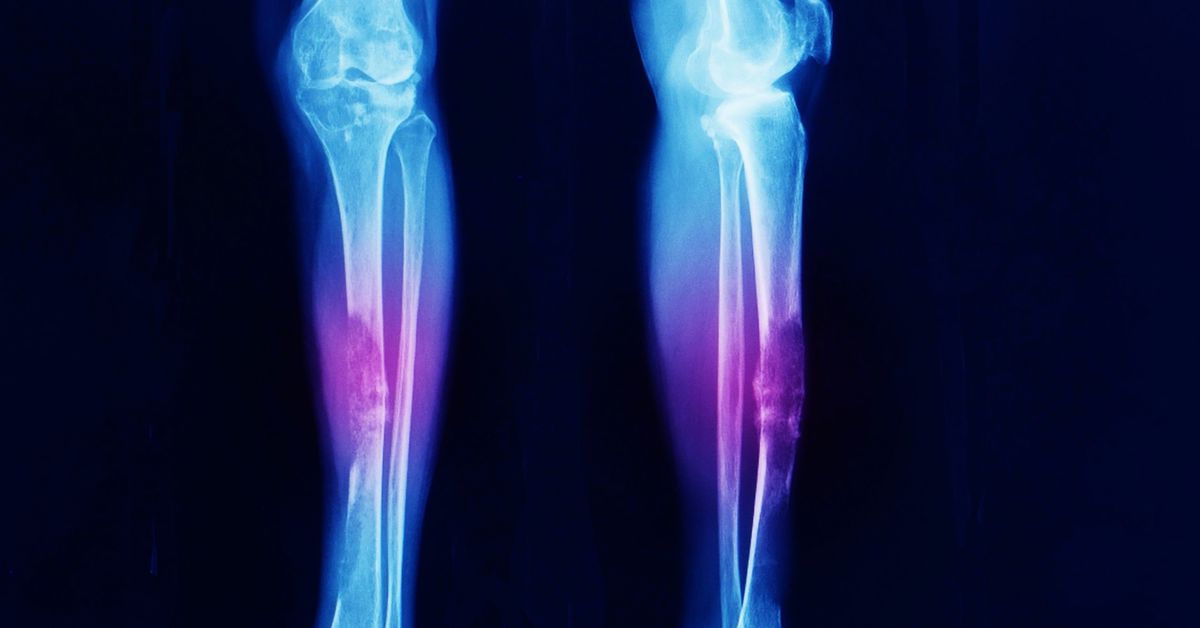

Kemik kistleri, kemik içinde sıvı dolu boşluklar olarak oluşur ve çoğu zaman belirti vermez. Küçük kistler uzun süre fark edilmeden kalabilir. Genellikle rutin röntgen veya başka görüntüleme yöntemleri sırasında tesadüfen ortaya çıkarlar. Büyüyen kistler ise kemik yapısını zayıflatabilir ve kırık riskini artırabilir.

Bu kistler, çoğunlukla uzun kemiklerde görülür. Kol ve bacak kemikleri en sık etkilenen bölgelerdir. Çocuklar ve gençler büyüme döneminde oldukları için risk altındadır. Bazı kistler tamamen asemptomatik olurken, bazıları hafif ağrı veya hassasiyet yaratabilir. Kistin büyüklüğü ve konumu, belirtilerin şiddetini belirler.